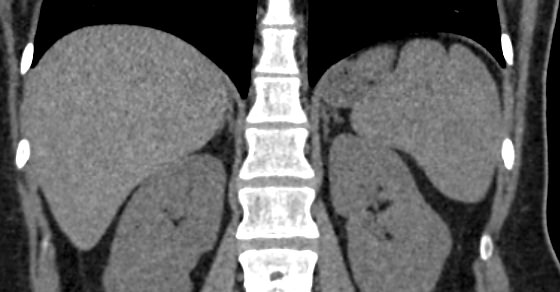

Нативная КТ (бесконтрастное исследование селезенки) показывает структуру органа достаточно однородно, без выявления незначительных изменений. Для большей информативности делают КТ селезенки с применением контрастных веществ.

На томограмме можно увидеть:

- нарушение целостности селезенки;

- кисты и крупные опухоли;

- кальцинаты;

- травматические и посттравматические изменения селезенки

- кровоизлияния внутрь брюшной полости

- отклонения от нормальных размеров.

- дополнительные дольки селезенки.